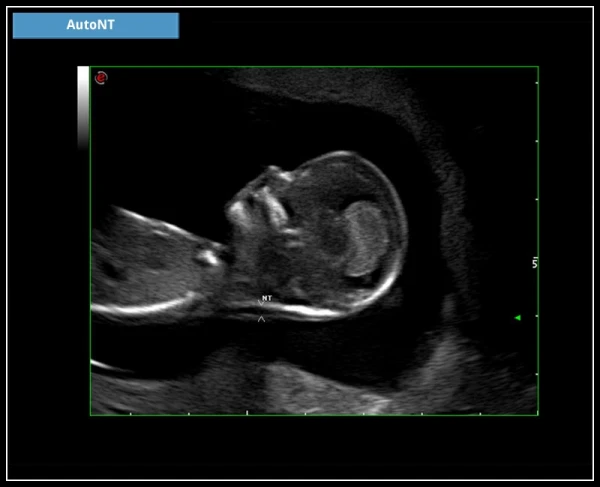

Технология полной автоматизации Zero-click

AutoNT: Автоматическое измерение толщины воротниковой зоны плода (NT).